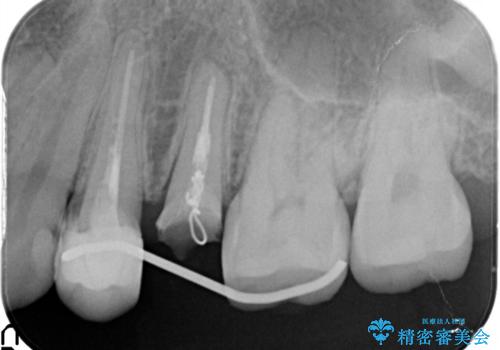

かぶせ物と詰めてある修復物を除去すると歯肉の中まで虫歯になっていました。

歯を部分矯正で引き上げて、虫歯を徹底的に取り除き、適合の良いかぶせ物を装着する計画としました。